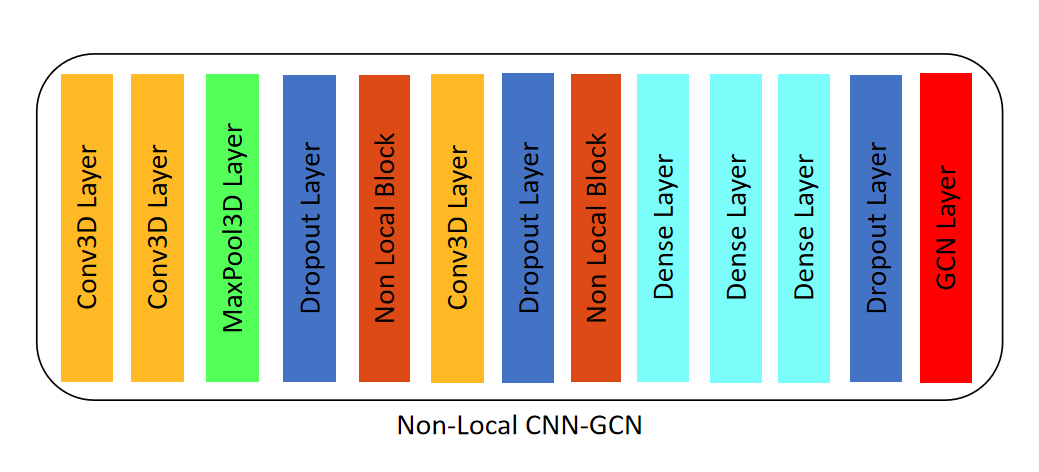

2.2.1 A Non-local CNN-GCN classifier

Traditional CNN network has limitation in capturing long range dependencies which extract the global understanding of visual scenes. In this paper, we consider both image information and connectivity information by connecting Non-local CNN and GCN. The Non-local CNN considers the global context information of the image, while the GCN module can learn the local and graph connection information. Combining these two modules together is useful for analyzing the vascular tree. In order to connect the Non-local CNN network with the GCN network, this paper adapt the end-to-end method of CNN connecting GCN proposed by Zhai et al.[13]. In the preliminary classification of A/V, the learning ability of the Non-local CNN-GCN method for the A/V features is better than that of the traditional CNN-GCN, Non-local CNN3D and CNN3D.

In this paper, for each point on the vascular topology tree, the orientation information of each node is used to extract the local patch of size S = [32, 32, 3] that should be perpendicular to the vascular direction from the CT image. A patch is labeled either artery or vein,i.e. {1, 2}, based on the label of the center voxel. We randomly select node b = 128 and their patches from our graph structure T as input, and we need the image patches of these neighbors n. Take NB of size b × n × s as the input to the Non-local CNN-GCN network, where n is the number of neighbors. Then the Non-local CNN-GCN classifier presented in this paper is trained and each center voxel is predicted to be an artery or vein. The Non-local CNN-GCN classifier adopted in this paper is shown in Fig. 8.